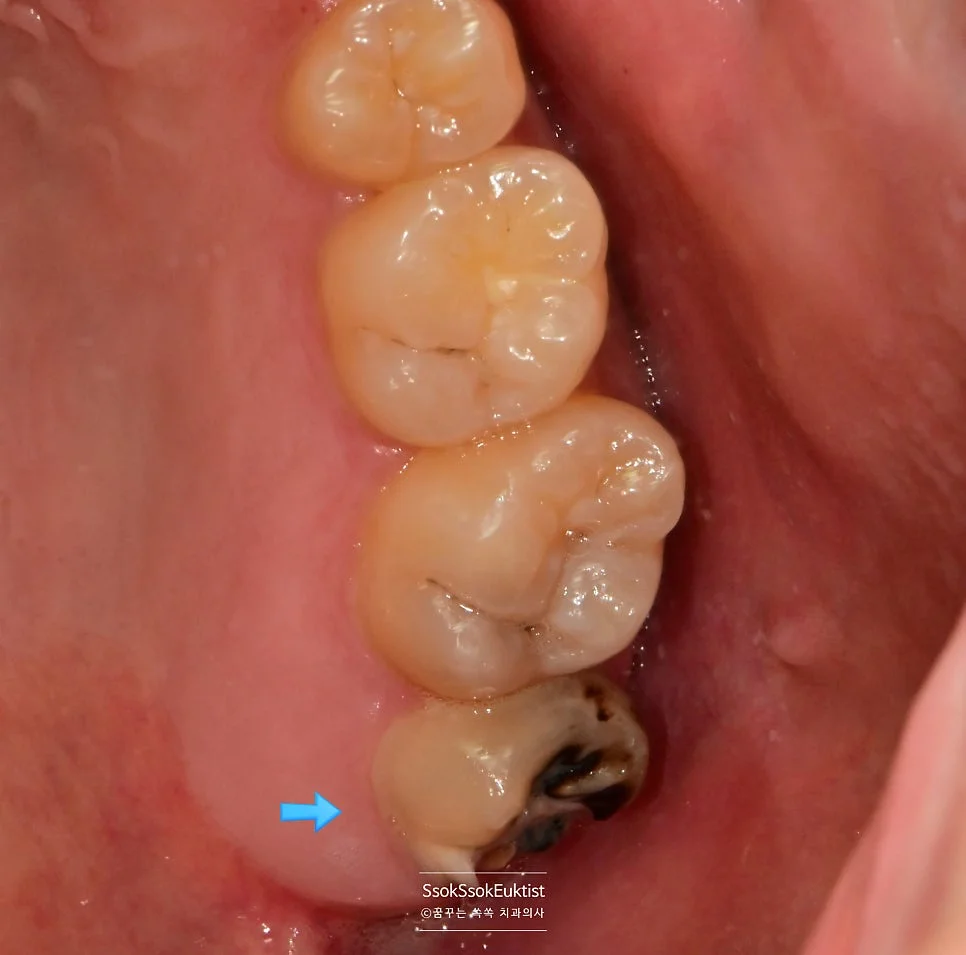

올바르게 난 위 사랑니의 모습을 자세히 촬영해 보면,

위 사랑니 충치 협측 근접 사진

위 사랑니 협측 — 충치가 선명하게 관찰

위 사랑니 충치 교합면 근접 사진

위 사랑니 교합면 — 치아머리에 충치 확인

치아머리에 충치가 선명하게 보입니다!

올바르게 맹출한 사랑니도 발치가 필요한 이유

치아는 올바르게 맹출했다 하여도 대합되는 상대 치아가 없는 경우 이렇게 쉽게 충치가 생깁니다!

서로 닿아 기능하는 것 자체로 치아머리 면의 세척 효과가 있는데, 혼자 덩그러니 있으면 그럴 수 없기 때문에 가장 먼저 충치가 생기게 됩니다.

예쁘게 나온 사랑니도 상대 위치의 사랑니가 없으면 발치를 추천드리는 이유입니다!^^